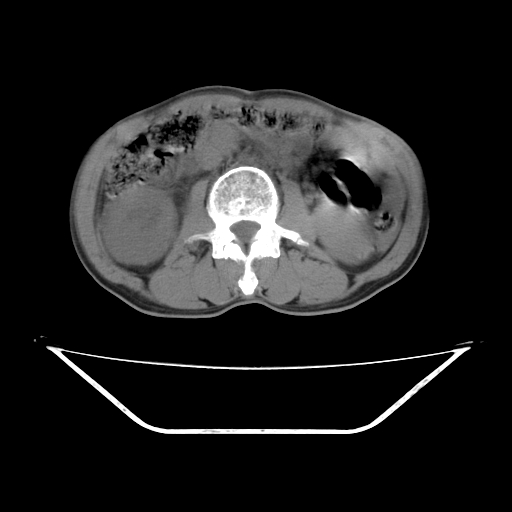

平扫

考虑右肾盂癌,肾动脉受侵,右肾功能减退,右肾盂输尿管积水,管壁增厚,考虑种植转移,应该把下面扫完的

支持右侧肾盂癌伴肾静脉瘤栓形成可能性大,右肾结石.肝右叶后段低密度影,不除外转移.

右肾盂旁ca并肾静脉瘤栓形成/肾功能降低。

右肾结石。

右肾盂癌,肾动脉受侵,右肾盂输尿管积水,管壁增厚,考虑种植转移

支持 右侧肾盂癌伴肾静脉瘤栓形成可能性大,右肾结石;肝右叶后段低密度影,不除外转移。

1.右侧肾盂癌伴肾盂积水。

2.肾脏功能减退,原因有:(1)肾动脉受侵。(2)肾静脉受侵(3)肾积水,等。本例,肾动脉显影较好,但受压明显;肾静脉无明显显示,受压或静脉癌栓,下腔静脉腔内未见明显充盈缺损。

3.右侧上段输尿管扩张,原因:(1)积水所致;(2)种植。